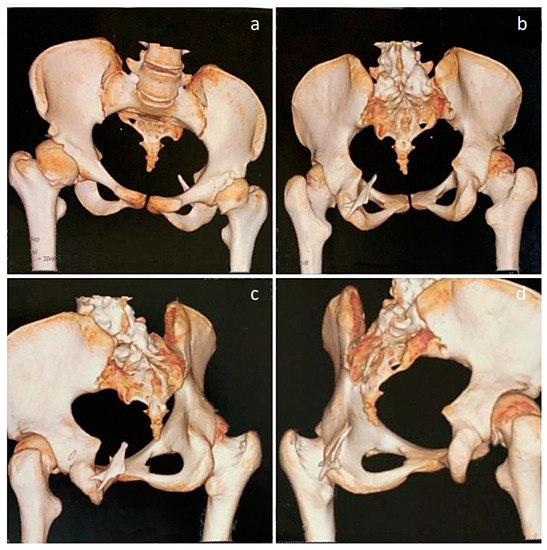

Figure 1. Three-dimensional CT images of the upper body, pelvis, and hip joints of an 18-year-old female with a clinicoradiological diagnosis of fibrodysplasia ossificans progressiva (FOP), an exceptionally rare genetic disease affecting 1 in 2 million people that is caused by a gain-of-function mutation in the gene that encodes activin A receptor type I (ACVR1) [1,2]. The disease is characterized by progressive heterotopic ossifications in various extraskeletal sites [3]. In the patient reported here, the disease initially presented as neck stiffness, followed by multiple episodes of back stiffness, the appearance of notable hard lumps, and finally, restricted movement in the right shoulder joint, with pain preceding stiffness in all affected locations. (ad) Thoracolumbar scoliosis and complete ossification of the disc spaces in the thoracic spine can be noted in both the anterior and oblique views, while fusion of the posterior elements, especially at the lumbar region, is evident on the oblique views. (b,d) The cervical spine appears to be fused, as indicated by fused lateral masses and posterior elements. (d,e) Heterotopic bone is observed, descending from the occiput, potentially indicating an ossified capitus muscle on the left side. (e) On the posterior aspect, a large mass of heterotopic bone is observed, corresponding to the location of the paraspinal muscles, branching upwards and fusing with the scapulae on both sides. On the right side, the heterotopic bone mass is fused with the humerus. (a,e) In addition, small, heterotopic bony projections are seen, originating from the first rib and pointing upwards. The rest of the upper limb was unaffected, allowing for full active range of motion in both elbows, wrists, and hands. Physical function, as measured by the SF-36 score, showed significant impairment (20/100), which affected her work and daily activities. As a result, her emotional and social well-being were also impacted. There were no obvious soft-tissue flare-ups at the time of presentation; however, she had hip pain that was described as moderate and interfering with daily activities.

Figure 3. Close-up 3D CT images of the rib cage, scapulae, and shoulder joints. (a) While the front of the chest wall appears to be relatively spared, there is an isolated mass of heterotopic bone on the left anterior chest wall adjacent to the sternum. (b) Oblique view of the chest wall, showing fusion of the right humerus to the heterotopic bone mass in the posterior aspect. (c,d) Oblique view, showing that the left shoulder joint and humerus are free of restricting ossifications. (d,e) Posterior views, showing that both scapulae are fused with the heterotopic bone extending from the lumbar paraspinal region. (e) Fusion of the right humerus to the heterotopic bone mass can be noted. (f) Posterior view of the chest wall, clearly showing fusion of the posterior elements of the spine.